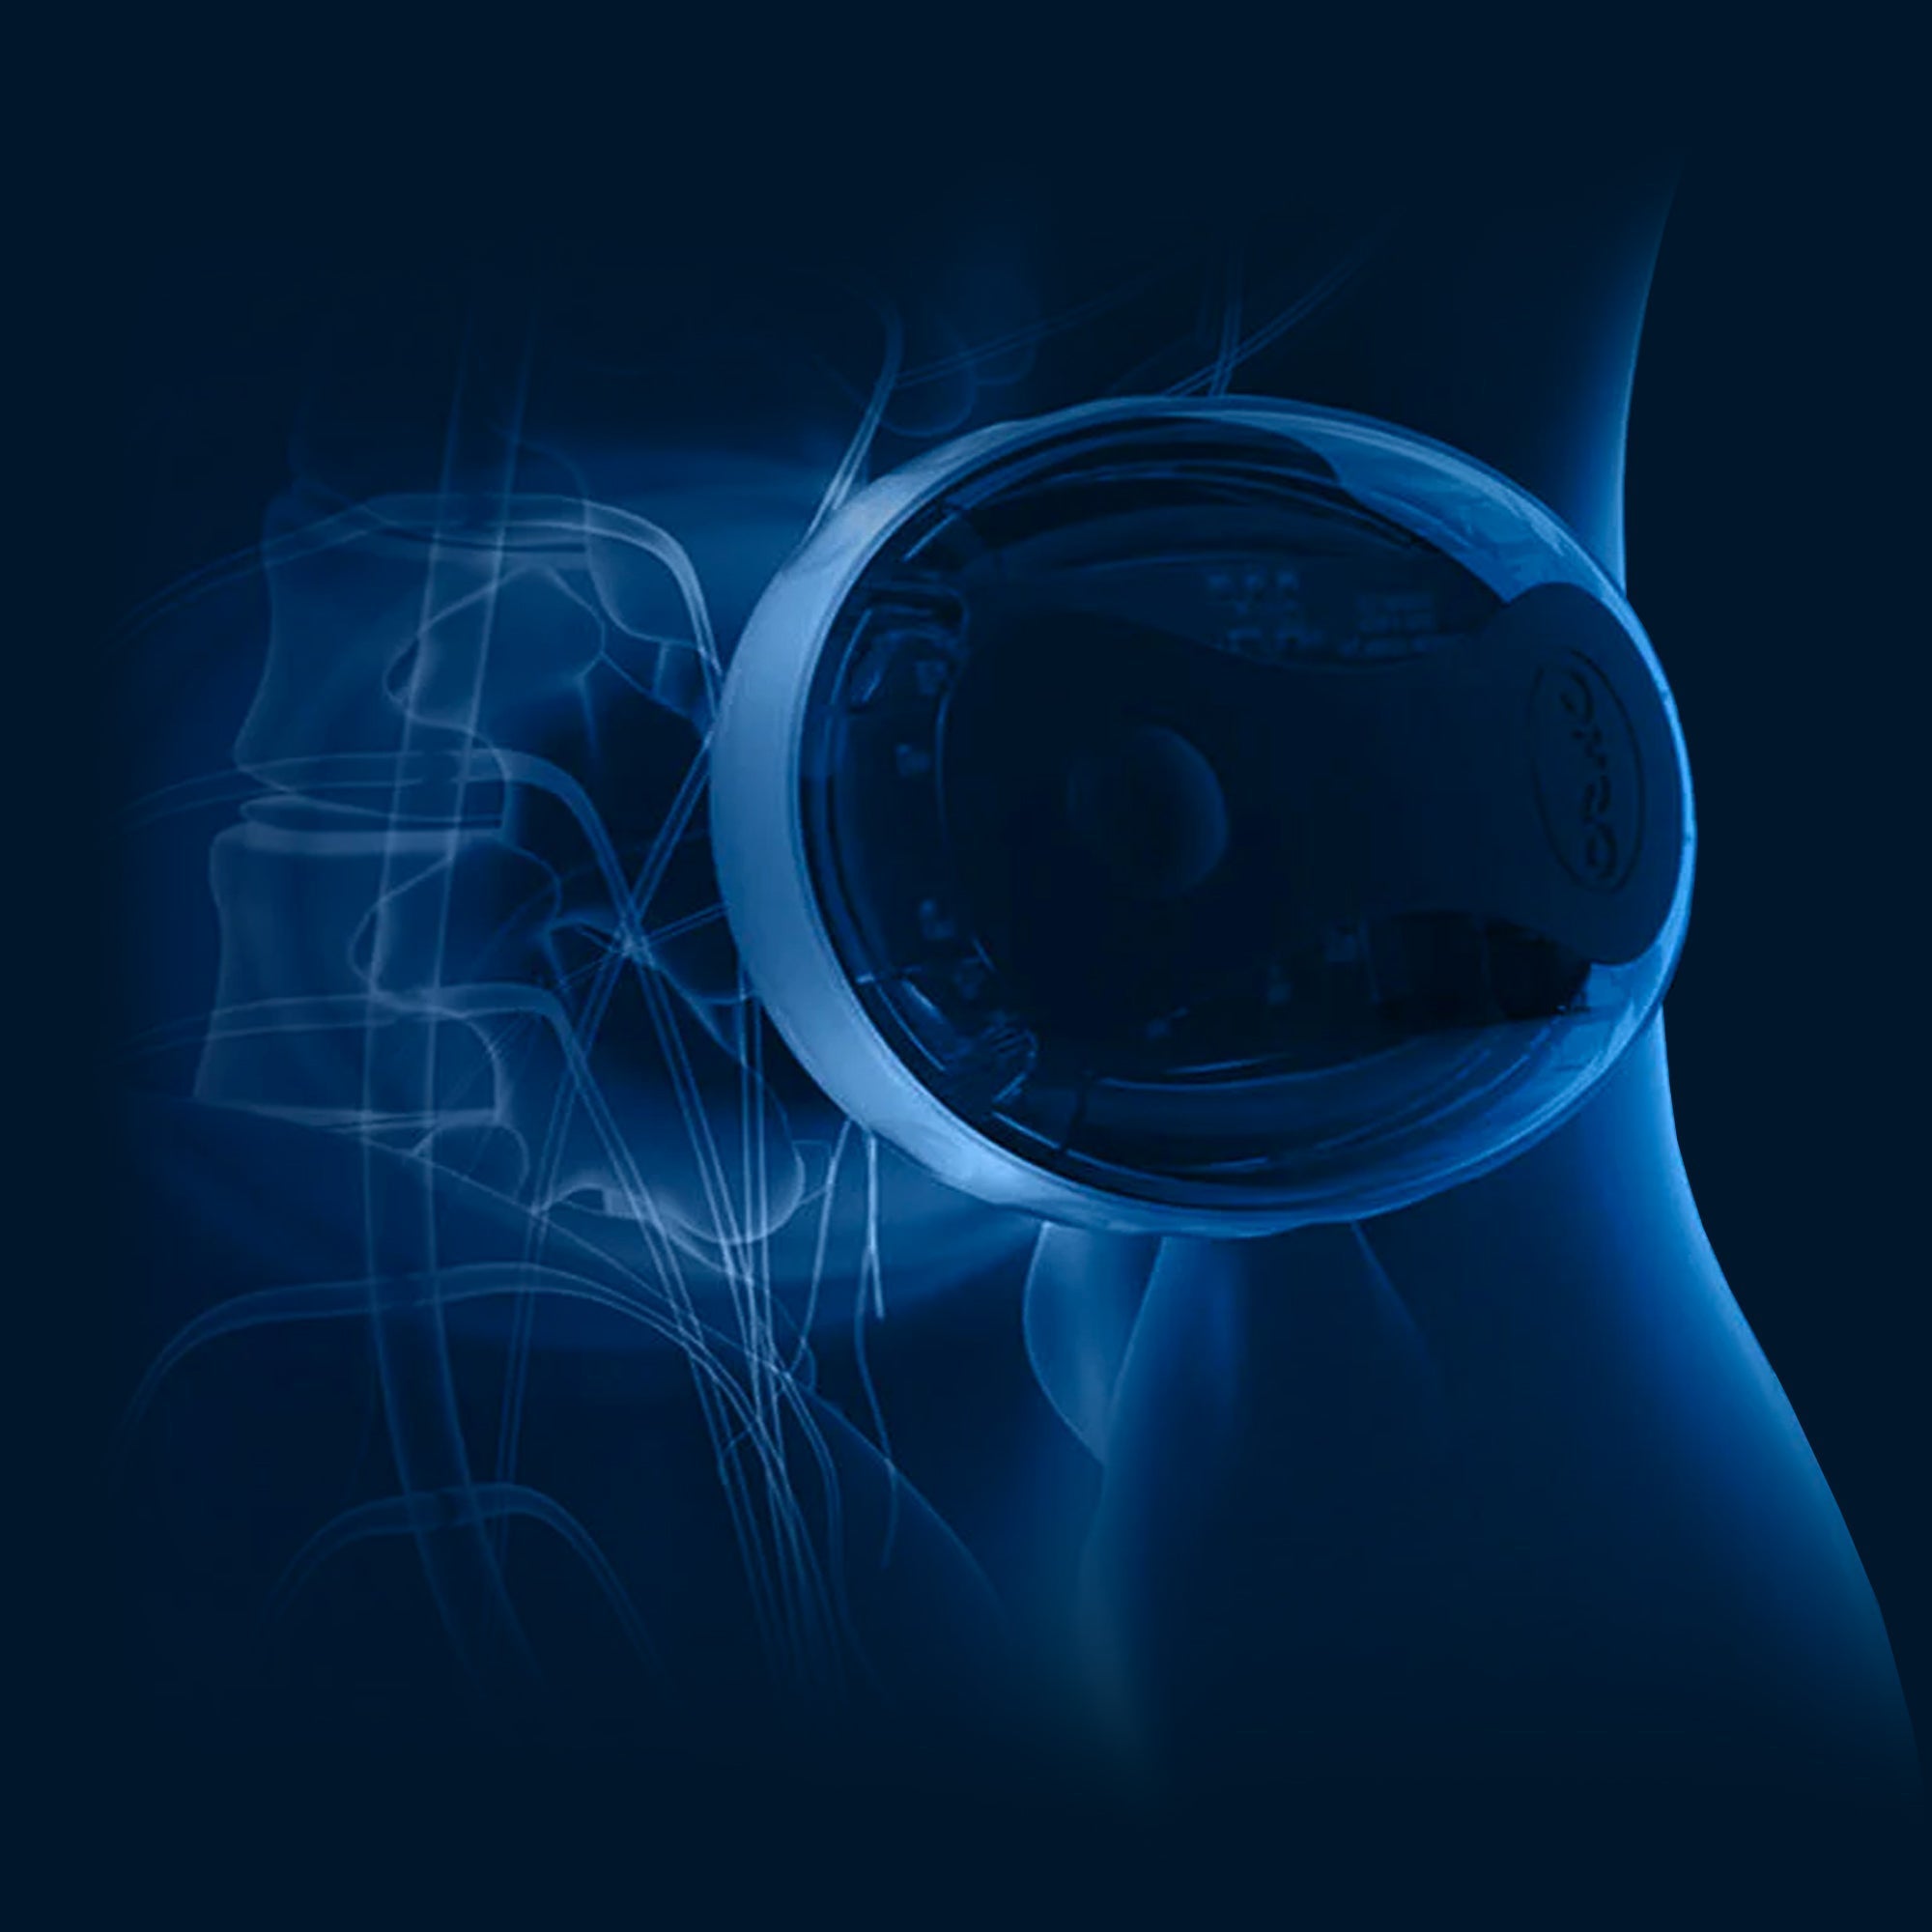

How OSKA Pulse Works

Oska Pulse addresses the root cause of pain:

True pain relief involves targeting the origin of your discomfort rather than merely blocking pain signals to the brain.

The Oska Pulse revolutionises healing! Experience the joy of dramatically reduced inflammation and pain, offering incredible relief from musculoskeletal injuries, wounds, arthritis, and endometriosis. Feel the difference as Oska Pulse accelerates your recovery after surgery, empowering you to get back to what you love faster and with greater ease. Embrace a brighter, more active future with the rejuvenating power of Oska Pulse!

Learn more about the science behind Oska Pulse and how you can use it as part of your treatment plan.